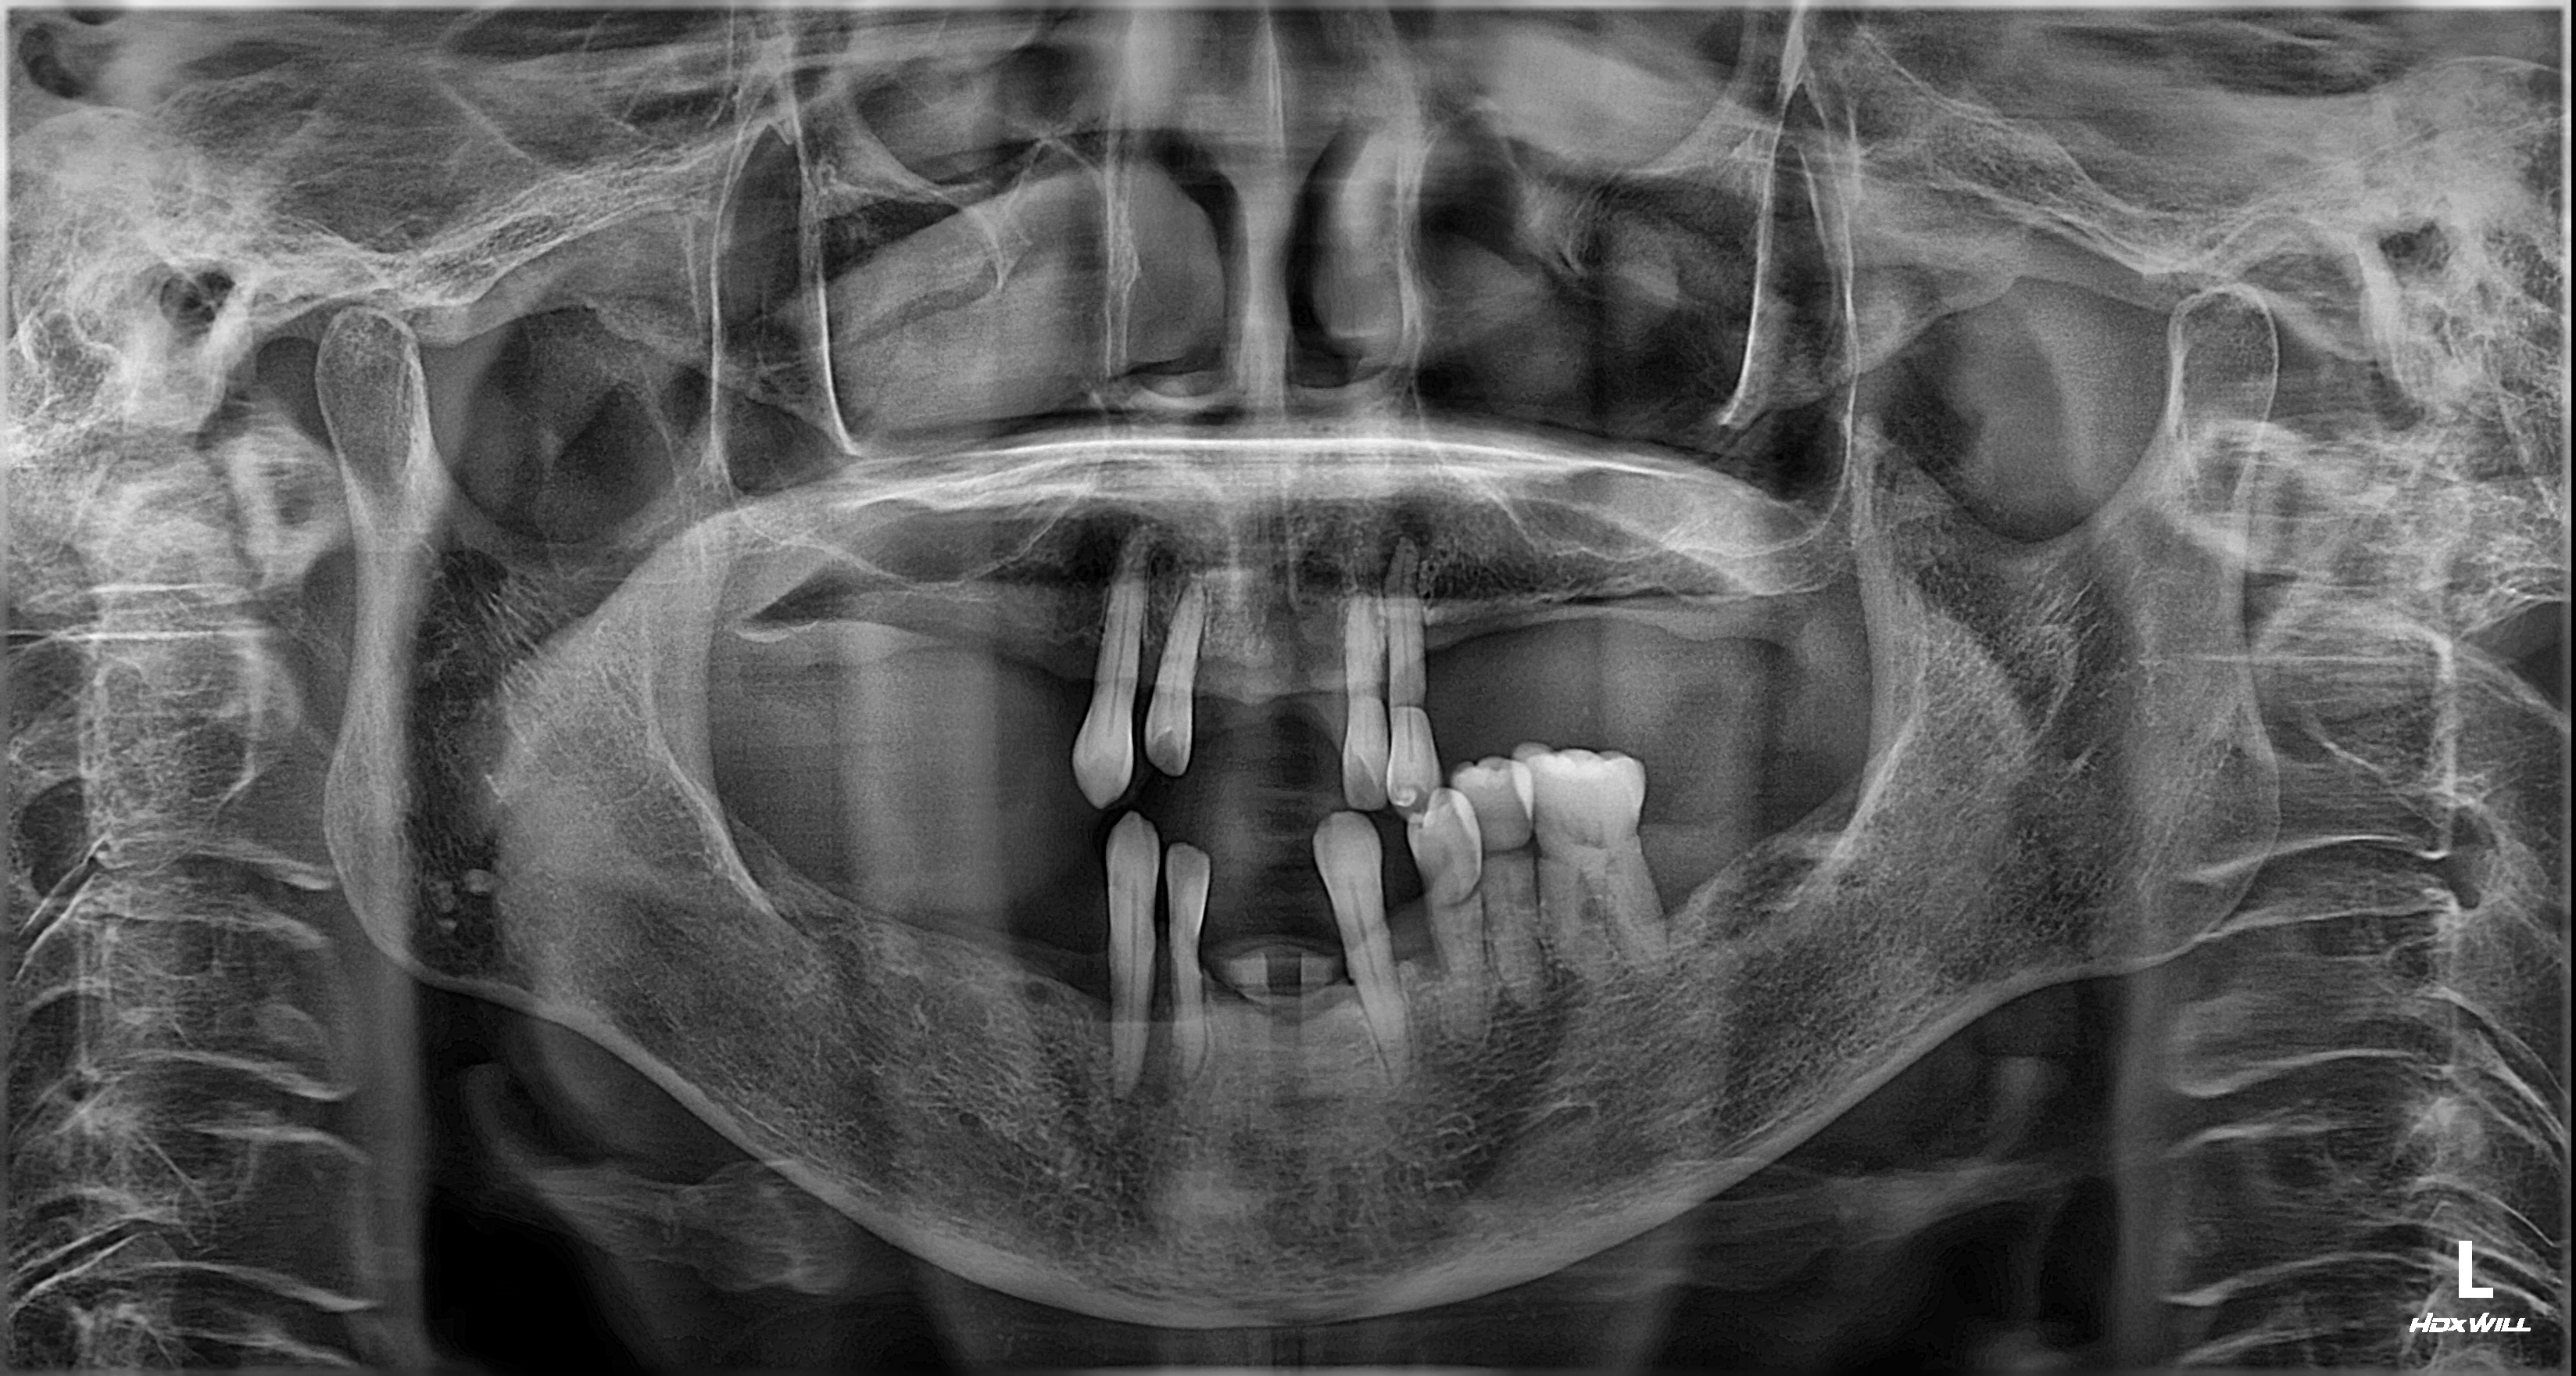

촬영일시: 2025.06.05